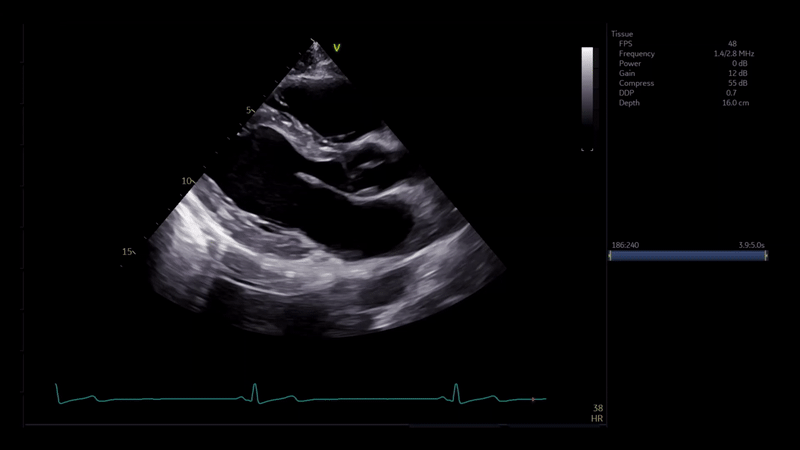

Confíe en nosotros para obtener una calidad de imagen incomparable

El diagnóstico y seguimiento clínico de sus pacientes requieren una imagen clara de su condición.

Por lo tanto, la calidad de la imagen debe ser de excelente calidad, especialmente para pacientes con diagnósticos más complejos.

El sistema Vivid™ Ultra Edition ha sido diseñado con una serie de tecnologías para ayudar a ofrecer imágenes de la más alta calidad para que pueda ver claramente y diagnosticar con confianza.

cSound ADAPT

Desarrollado para corregir las desviaciones de ultrasonidos que pueden degradar la calidad de la imagen. Así puede obtener un contraste sin precedentes y una resolución de imagen en tiempo real en cada paciente.